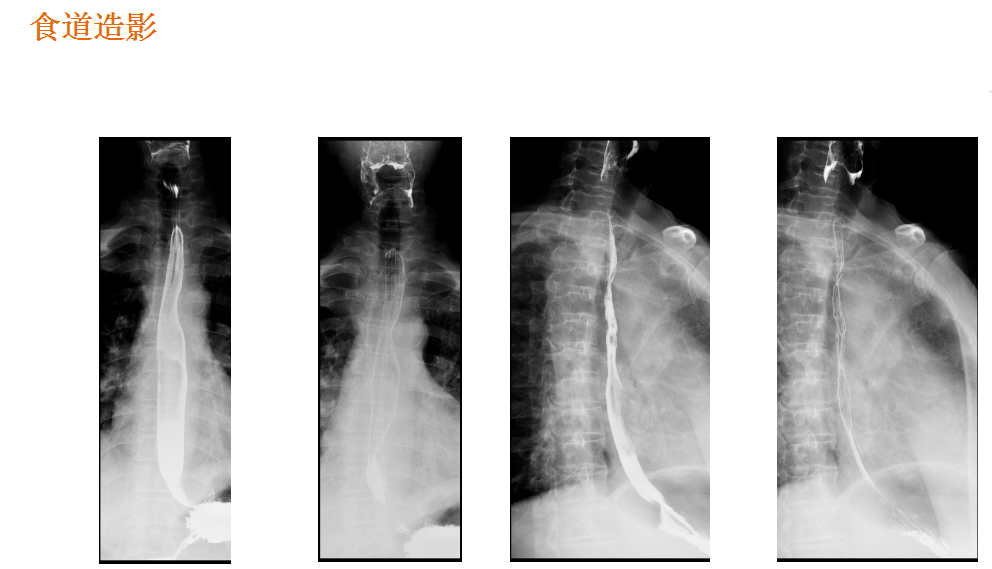

该设备属于多功能X线机,除具有传统数字胃肠机所有功能外,还有DR平板探测器X线摄影所有功能,主要用于消化道气钡双重对比造影、全脊柱拼接摄影、全下肢拼接摄影、ERCP、泌尿系造影、“T”管造影、钡剂灌肠、四肢造影、子宫输卵管造影等各类检查,是检查消化道溃疡、肿瘤、异物等疾病的主要方法之一。

检查过程中,该设备能根据检查部位不同,调整采像速度,动态观察脏器生理运动是否发生改变,对一些常规造影中所重叠影像进行削减,提高影像质量,并将检查过程中采集的图像,通过数字化处理后让图像更加清晰,并能满足特殊病灶诊断治疗的需要和特殊造影检查,提高诊断准确率,降低误诊率和漏诊率。

在临床方面,强大的图像处理功能可以完成临床各种造影的需求。